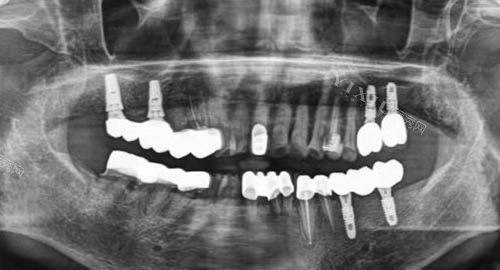

矫正前的准备工作十分重要。齐全的口腔检查是基础,需要处理现有的龋齿、牙周炎等问题。影像学检查如全景片、侧位片和CT扫描能帮助医生制定更准一些方案。取模或智能化扫描记录初始牙齿状态,为后续结果对比提供依据。与医生充分沟通期望和顾虑,确保双方对治疗目标有共识。